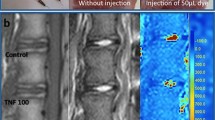

MRI assessment

Representative sagittal images of color-coded T2 maps show a different degree of signal intensity of the NP, depending on disc level and timepoint (Fig. 6). Higher T2 values, as indicated by red pixels, were uniformly observed in the NP of CA (L1–L2) and NI control (L5–L6) discs throughout the experimental period. However, red pixels, replaced by orange or yellow pixels, were identified in the NP of MIA 0.01 mg- or 0.1 mg-injected discs at 8 and 12 weeks post-injection. A significant loss of red pixels, replaced by blue to black pixels, was found in the discs injected with 1.0 mg of MIA.

Two-way repeated-measures ANOVA showed that the T2 value of the whole disc time-dependently decreased (P < 0.01) and differed significantly depending on the disc level during the observation period (P < 0.01) (Fig. 7). T2 values of CA control (L1–L2) discs showed no significant changes compared to NI controls (L5–L6) discs. The intradiscal injection of MIA 1.0 mg (L4–L5 discs) significantly decreased T2 values compared to those of CA control (L1–L2) discs (P < 0.01) (Fig. 7). Timepoint analysis showed significant differences in T2 values among the groups at week 8 post-injection (P < 0.01). The mean T2 value of MIA 1.0 mg-injected discs (L4–L5) was significantly lower than that of MIA 0.01 mg-injected discs (L2–L3) and CA control discs (MIA 0.01: P < 0.05, CA: P < 0.01) (Fig. 7). A similar trend of T2 values of MIA-injected discs was identified at 4 and 12 weeks post-injection; however, it did not reach statistical significance among groups (4 weeks: P = 0.07; 12 weeks: P = 0.07).